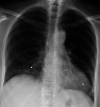

Case of Severe Treatment-Resistant Cryptogenic Organizing Pneumonia

Cryptogenic organizing pneumonia is a rare interstitial lung disease with different onset of symptoms, which responds rapidly to glucocorticoid treatment. We present a case of cryptogenic organizing pneumonia which manifested as a progressive 3-year dyspnea that ultimately has led to acute respiratory failure. Moreover, treatment with prednisone for this patient exhibited slow onset of the effect.